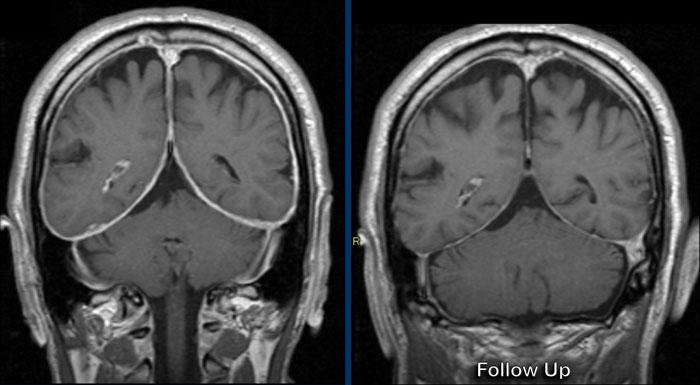

Các hình ảnh này của một nam giới 58 tuổi mắc ung thư phổi.

Có hai tổn thương bắt chước hình ảnh của u màng não.

Tiếp tục xem các hình ảnh theo dõi…

Trên hình ảnh theo dõi sau 2 tháng, tổn thương phát triển đáng kể.

Hiện tại bờ tổn thương không đều.

Đây hóa ra là di căn màng cứng.